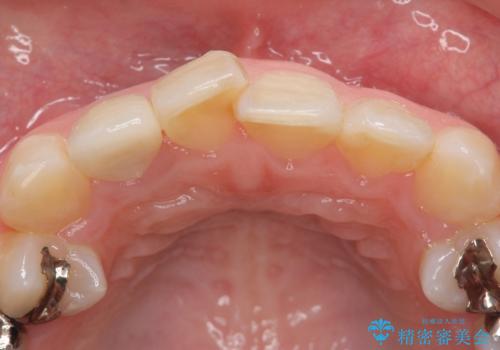

- 右上2番目の歯の被せ物と歯茎の間の継ぎ目が気になるといらっしゃった方の症例です。

再根管治療は希望されなかったため、クラウン除去後、オールセラミッククラウン(スペシャル)による補綴を行いました。

- オールセラミッククラウン(スペシャル)…¥130,000、仮歯…¥10,000、ファイバーコア…¥20,000費用は治療当時の料金となります